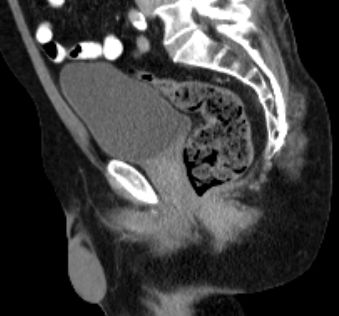

| CT | 66jähriger Mann, dass er seit einigen Wochen Blut im Stuhl gehabt habe.

Eine Koloskopie vor 6 Wochen habe einen unauffälligen Befund ergeben.

Bei der Austastung findet sich ein 5 cm großer schüsselförmiger Krater mit wulstigen Rändern.![]() | ||

Zusätzlich ein 2,5 cm großen Lymphknoten in der rechten Leiste medial der Vena femoralis. ![]() |